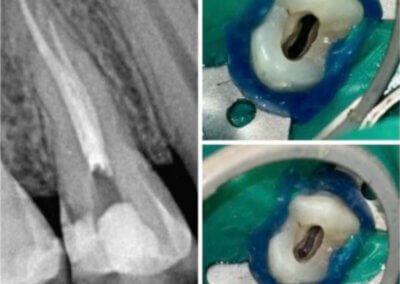

Utilizarea tehnicilor moderne asigură un tratament rapid, precis și confortabil pentru pacient.

Reconstituirea coronară cu materiale de calitate conferă rezistență pe termen lung.